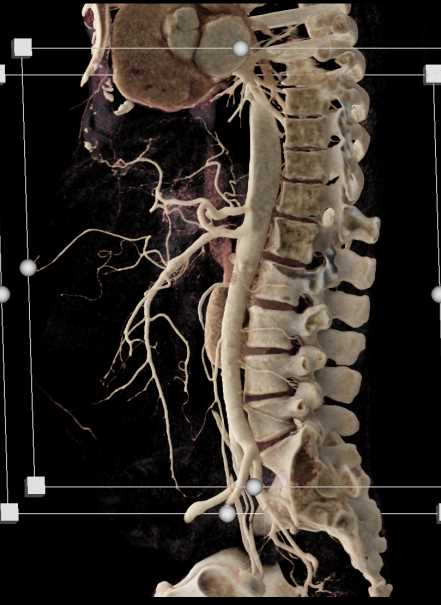

SMA Stenosis